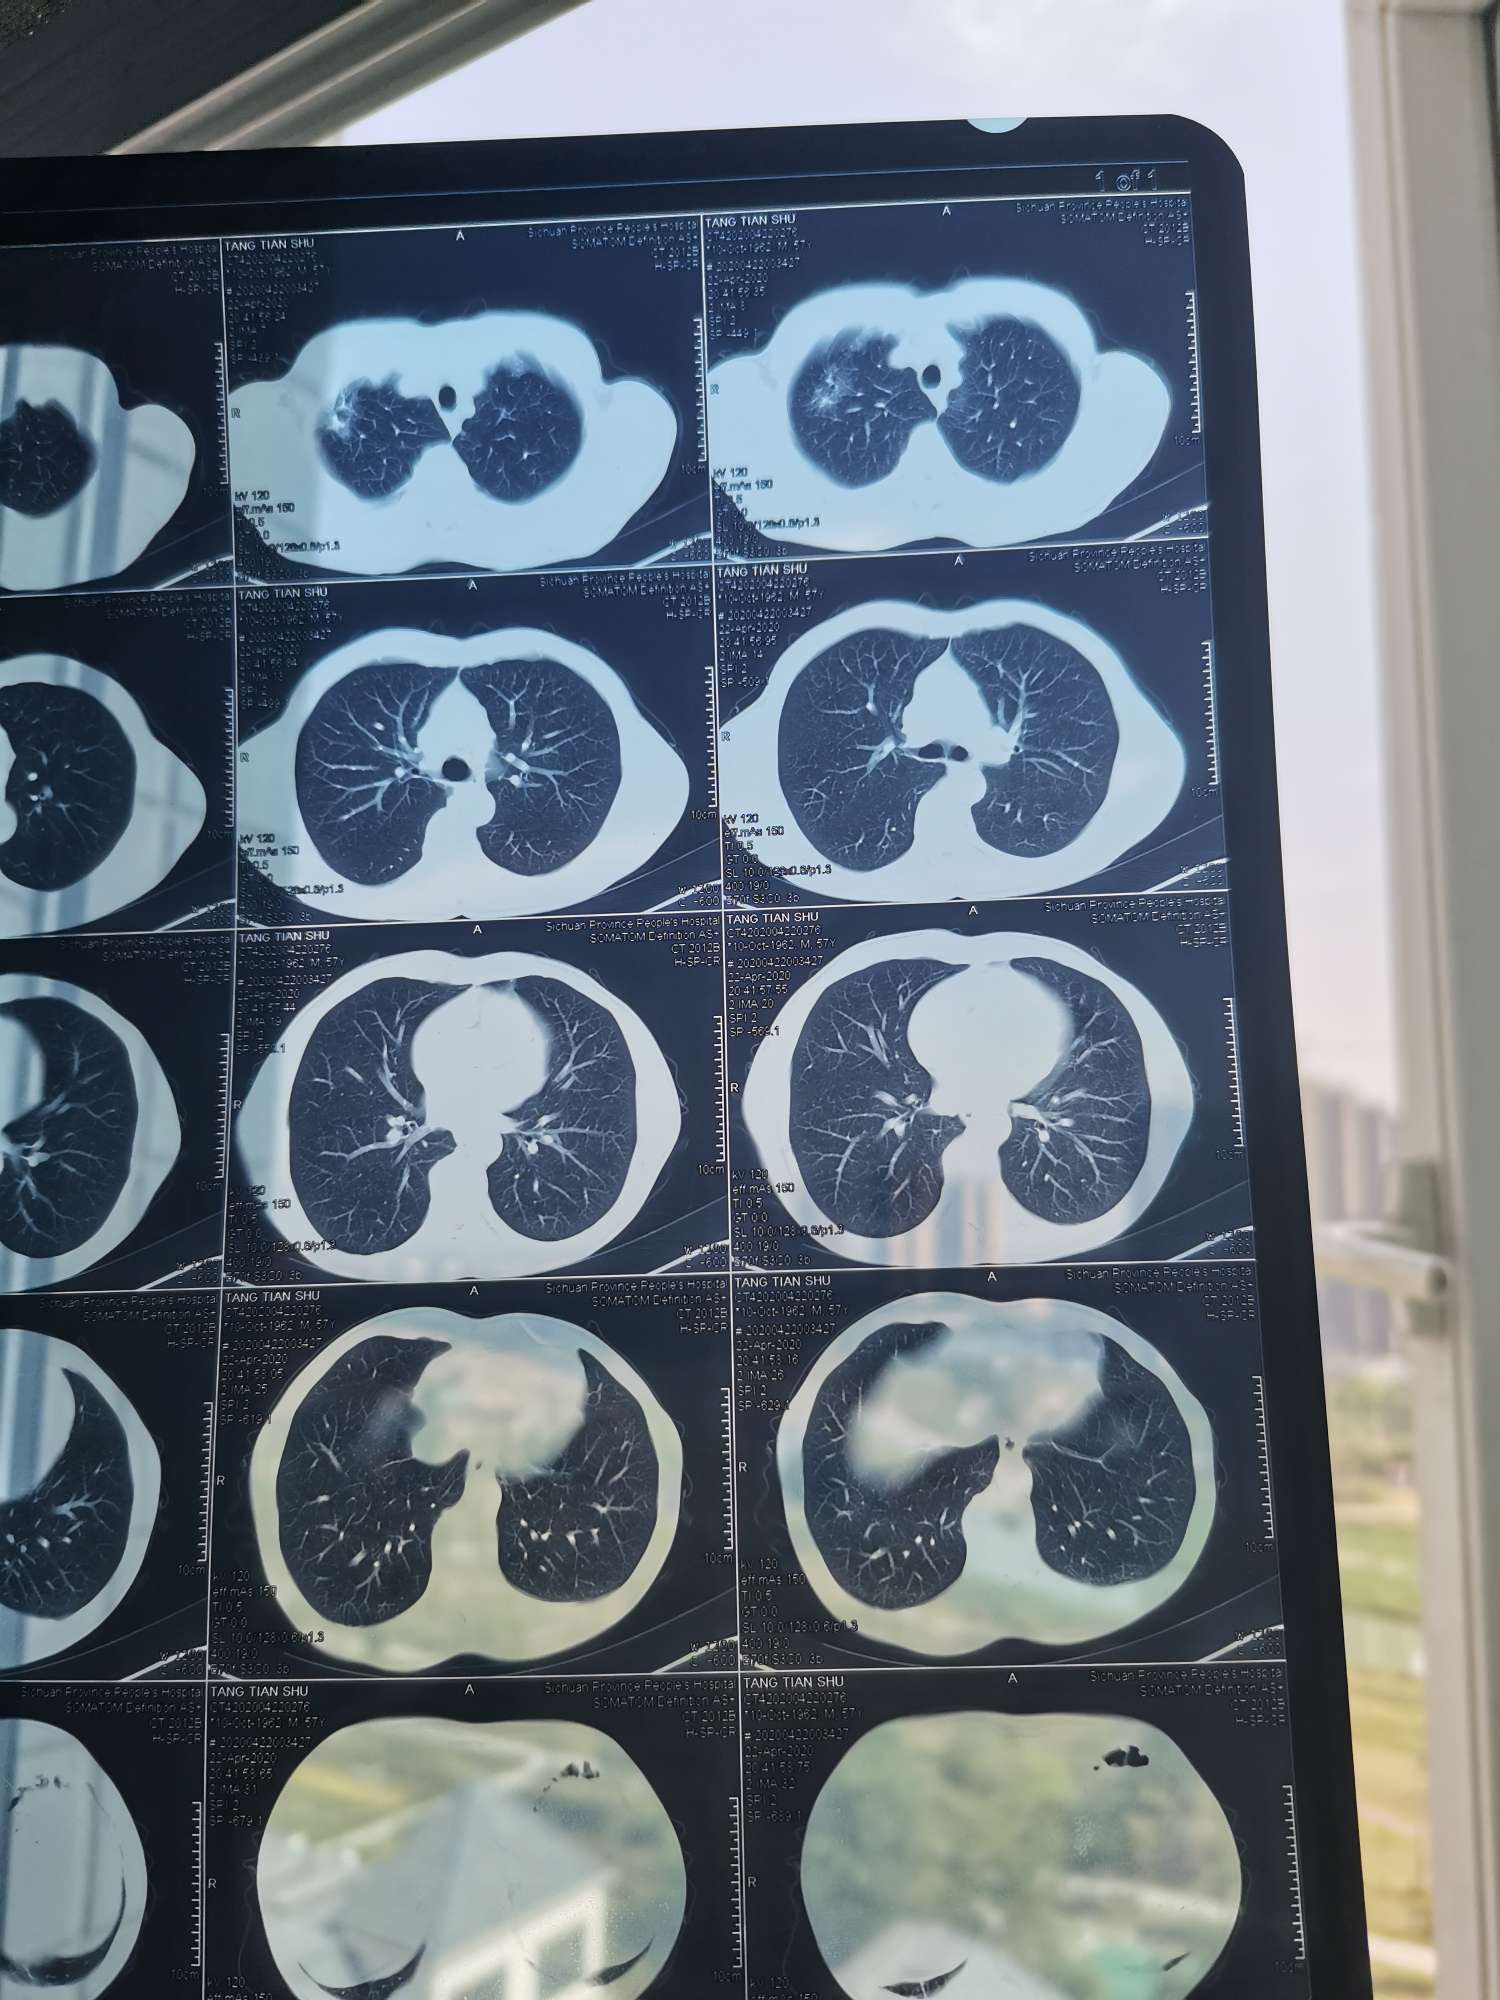

是否为腺癌,影像上不好判断,病理诊断为金标准,单从报告单上看,还不严重,可能有手术的机会

看ct结果没有转移,能做手术就尽快手术,一次性切除病灶!后期采用化疗和靶向治疗防止复发,以后定期复查不用担心太多!

是不是癌标准是取组织病理确诊,另外可查血肿瘤指标超出正常范围的话癌的可能性大,早期未转移手术是最佳选择,判断有无远端转移可以pet-ct。

是不是恶性肿瘤需要完善检查,才能定性。而且癌种不能通过影像确定,需要病理检验才能确定

请大家看看这个是不是肺腺癌?如果是的话分期严不严重分期